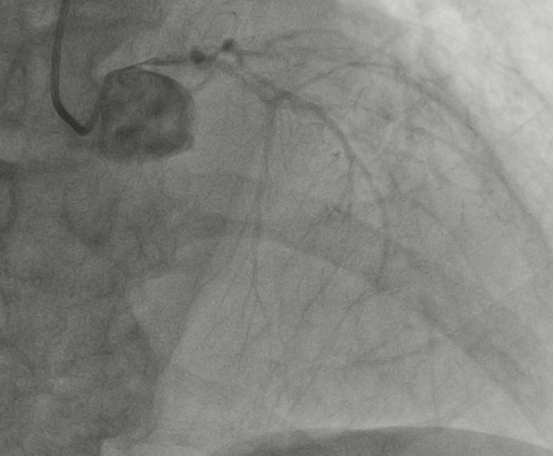

10月24日凌晨1时,67岁的姜大叔突发胸痛并持续加重,伴有大汗,在家忍受了4小时后才拨打了120电话送到我院,经绿色通道行急诊冠脉造影见:右冠急性闭塞、左主干重度狭窄、前降支中远段慢性闭塞、回旋支近段重度狭窄。一边血管堵塞一边血管开口接近闭塞,相当于心肌只有很少血液供应,随时有猝死风险。

图1:右冠闭塞